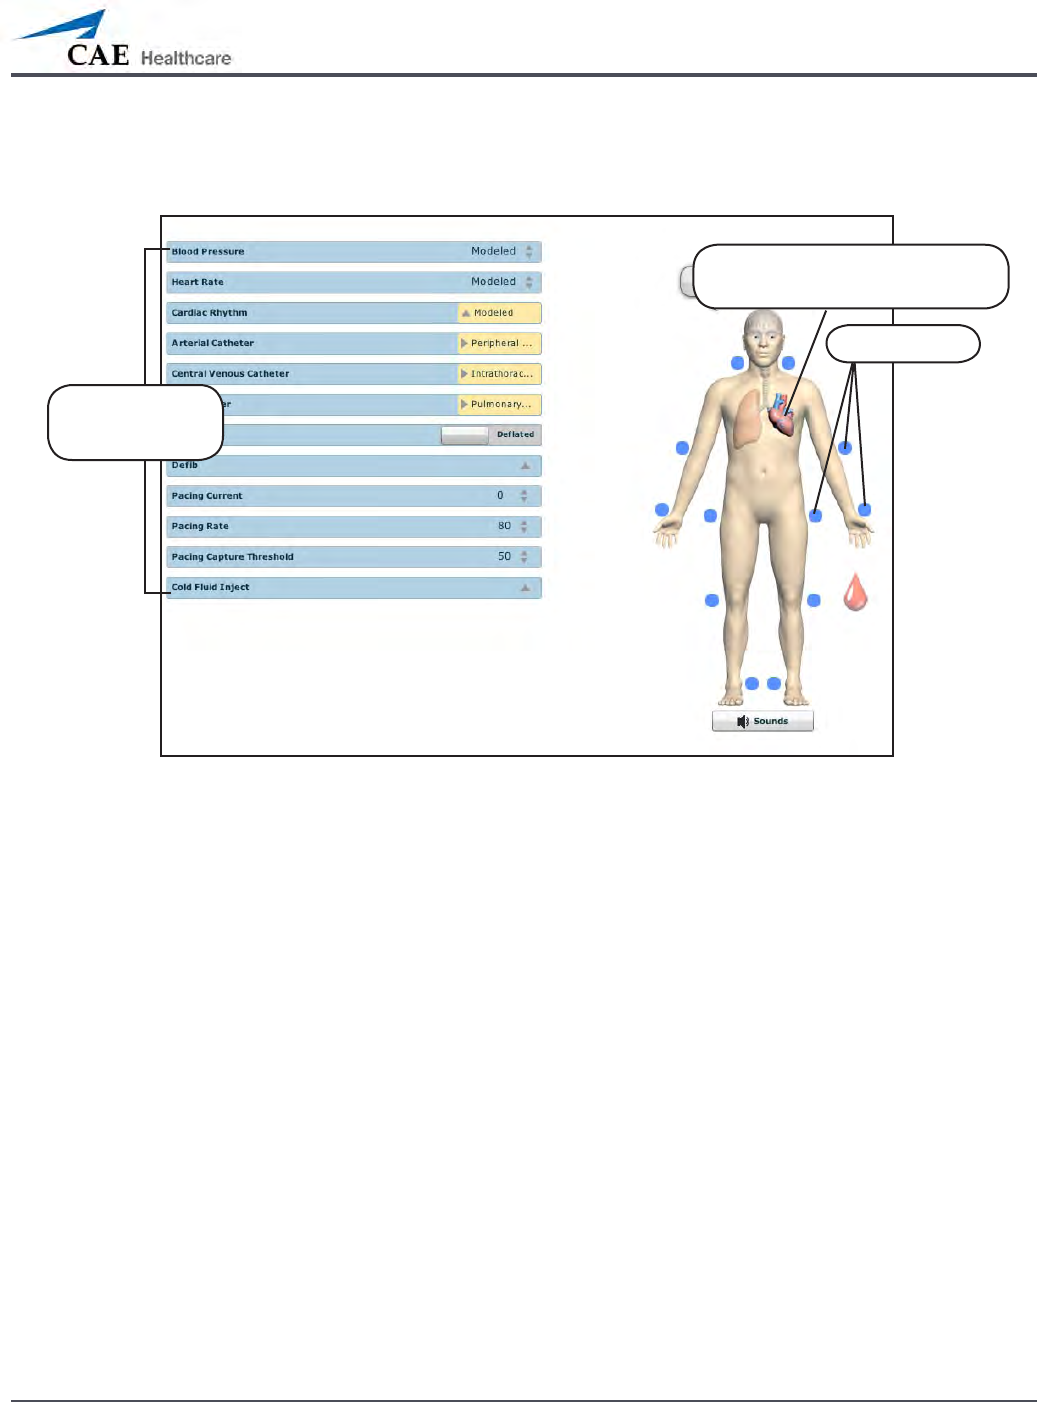

To access the Cardiovascular parameters of METIman, on the Run screen, click the heart on the

human form. The cardiovascular features appear on the Run screen.

The Cardiovascular View (Prehospital)

Click the heart to access the

Cardiovascular view

Pulses

Cardiovascular

parameters